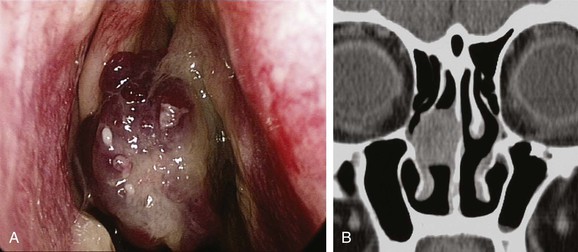

Hereditary hemorrhagic telangiectasia (HHT) is an autosomal-dominant multisystemic disorder characterized by telangiectasia that affects cutaneous and mucosal surfaces and arteriovenous malformations in the pulmonary, cerebral, and hepatic circulations (Fig. 42-23). The most common symptom in this population is epistaxis, which affects more than 90% of individuals. The severity of attacks is variable, and episodes of epistaxis can be functionally and socially debilitating for the patient and may require frequent hospital admission; in addition, a set of patients exists for whom the bleeding is intractable.99 Many methods of treatment for epistaxis as a result of HHT have been described in the literature; these include medical strategies, such as the use of hormonal manipulation and antifibrinolytic agents, as well as surgical options, which include laser coagulation (Fig. 42-24),100 septodermoplasty,101 and nasal closure,102 but no one method has proved itself entirely successful or without significant side effects.

A recent prospective study by Hitchings and colleagues99 investigated the effect of various surgical options on quality of life scores in these patients. The authors have concluded that nasal closure should be offered to patients with moderate to severe epistaxis that has proved unresponsive to other treatment options (bipolar or laser coagulation treatment, septodermoplasty), and subjectively 88% (7/8) of patients treated with nasal closure reported a complete cessation of their nosebleeds. Closure of the nasal cavity, the Young procedure, is based on the principle that the absence of desiccating airflow through the nasal cavity prevents the initiation of mucosal breakdown overlying the fragile telangiectasias.102 An alternative to nasal closure is the use of nasal obturators.103 In recent years, the monoclonal antibody bevacizumab has been advocated in HHT for intractable epistaxis, with use both topically104 and by local injection.105-107 In addition, some evidence supports the use of tamoxifen to reduce the need for blood transfusions.108